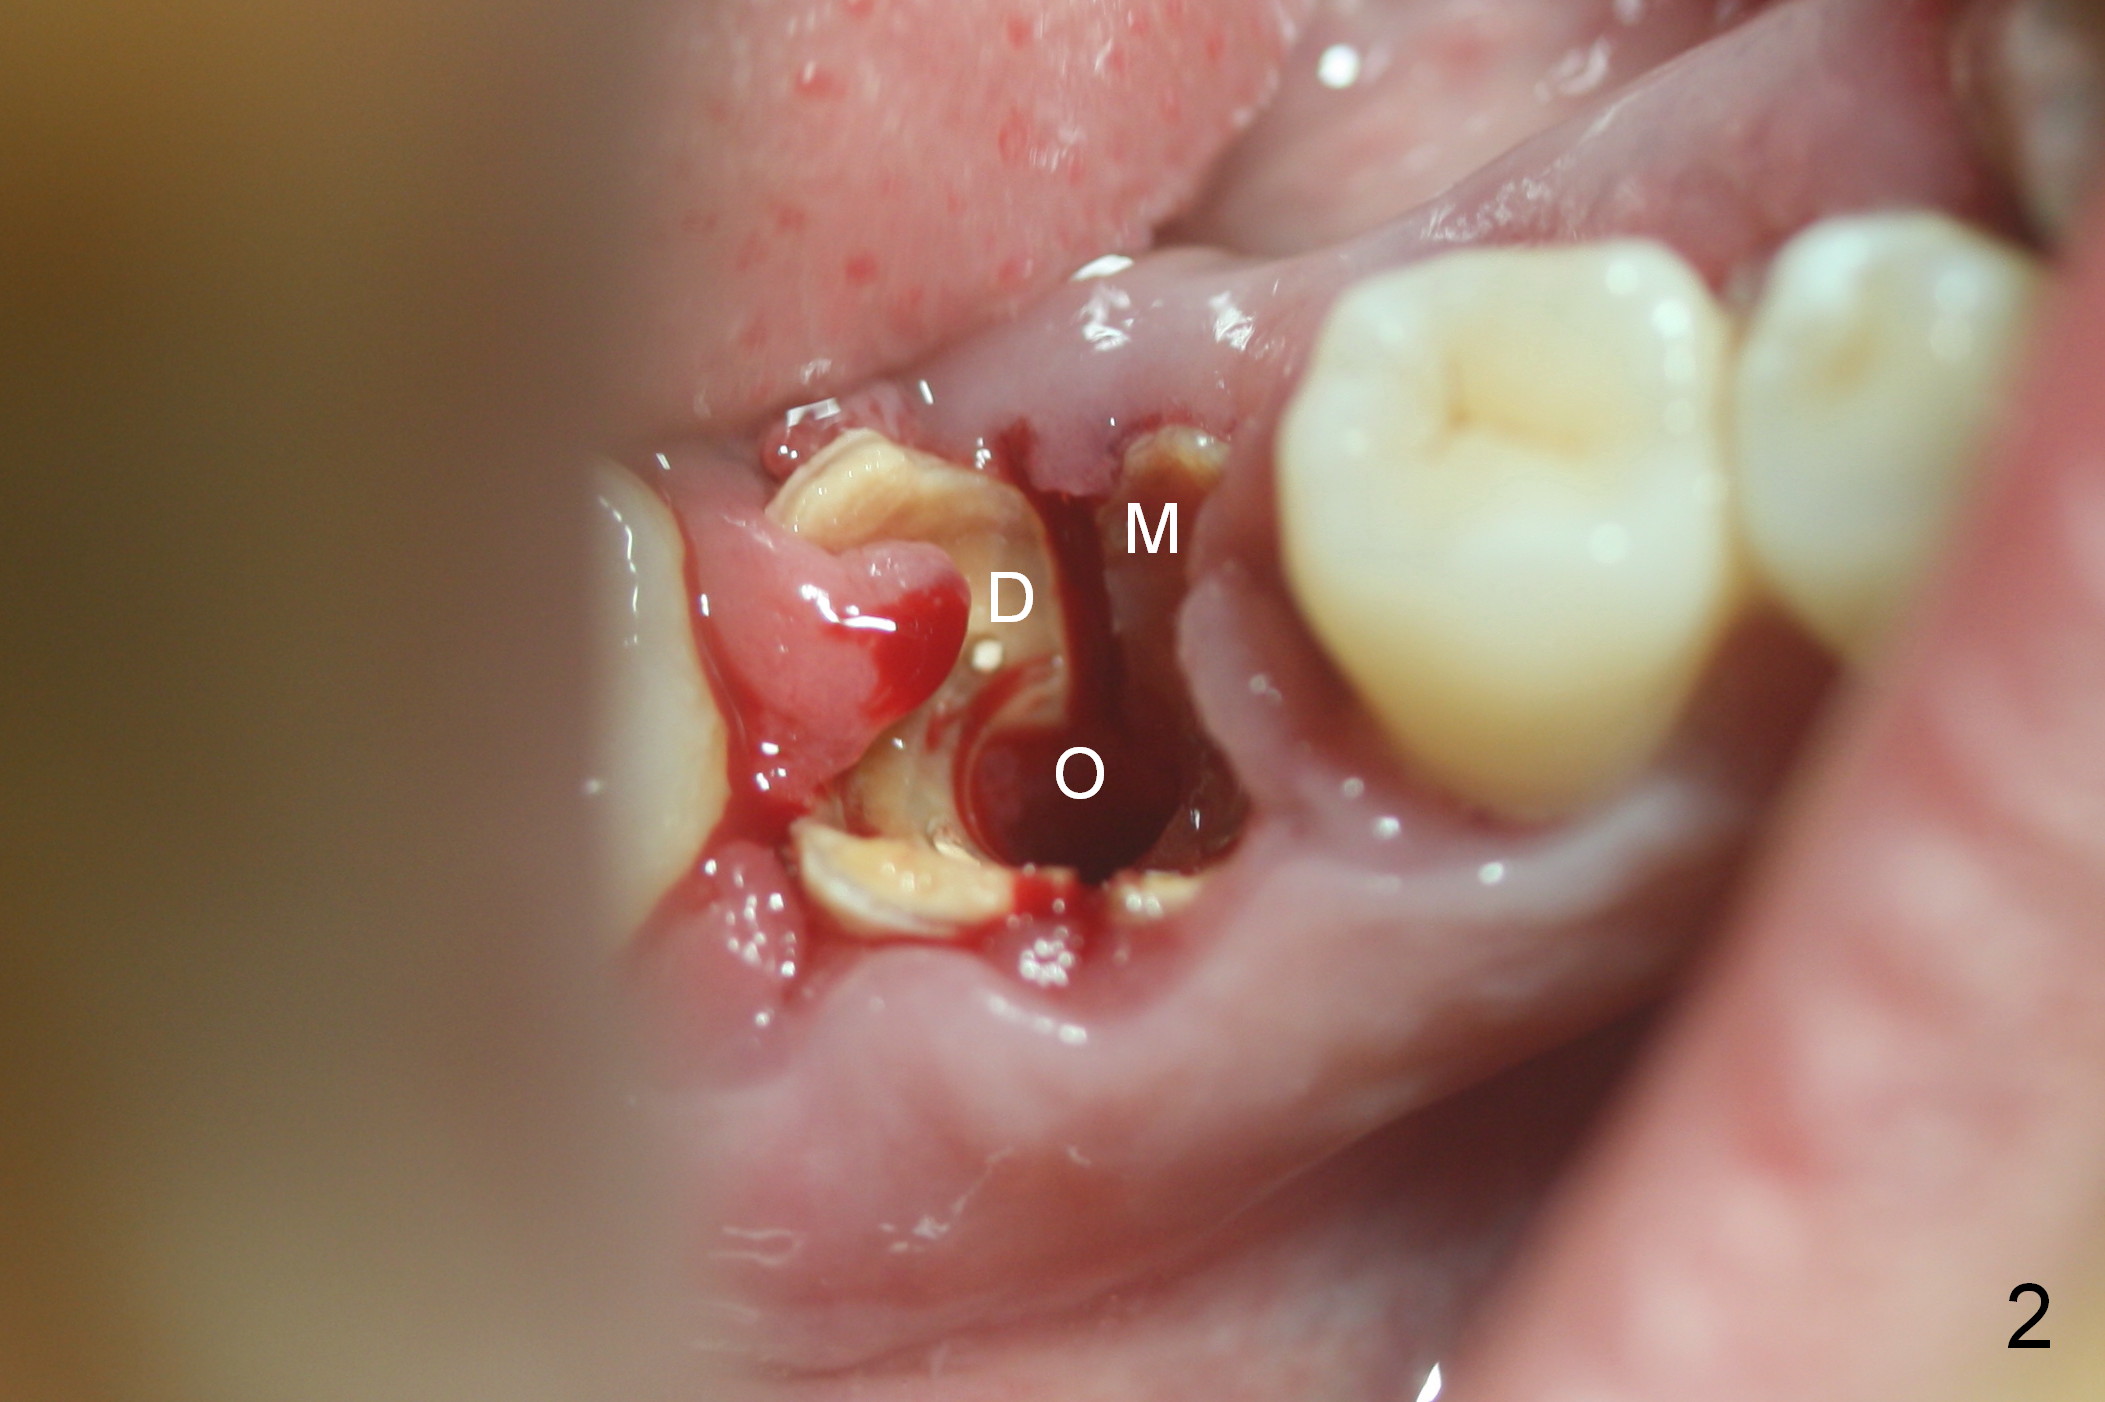

After cleaning the root surface with a surgical curette, a 1.6 mm pilot drill is used to start osteotomy (O) between the mesial (M) and distal (D) roots, followed by a marking bur and 3.8 mm Magic drill 13 mm deep (Fig.1,2). Following root removal, the 3.8 mm drill is reused for 11 mm (Fig.3). After deepening the osteotomy for another 2 mm, a 4.5x13 mm implant is placed with insertion torque of 50 Ncm, followed by allograft (*, .5-2 mm) and a 5x4(2) mm abutment (Fig.4,5). An immediate provisional is fabricated to close the socket (Fig.6 P (lock in)). The detached buccal gingiva (Fig.6 *) is kept in place by applying periodontal dressing (Fig.7 *). Red dashed lines in Fig.1, 3, 5 represents the superior border of the Inferior Alveolar Canal and Mental Foramen.